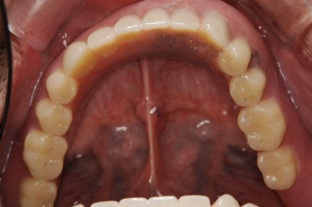

前歯しか残らなかった方です。奥歯にインプラントをしなければならないのですが、普通のインプラント治療であればサイナスリフト(骨移植)して1年待ってそれからインプラントを埋入してと1年半くらいかかってしまいます。ですが、オールオンフォーの治療を行っている医院であればこのような治療を施すことが可能となります。

この方は結局、all on 4 を応用し、奥歯に両側2本のインプラントを傾斜埋入して、それにマグネットをつけました。これなら骨移植をせずにインプラントが可能になり、3ヶ月ほどで終了できます。